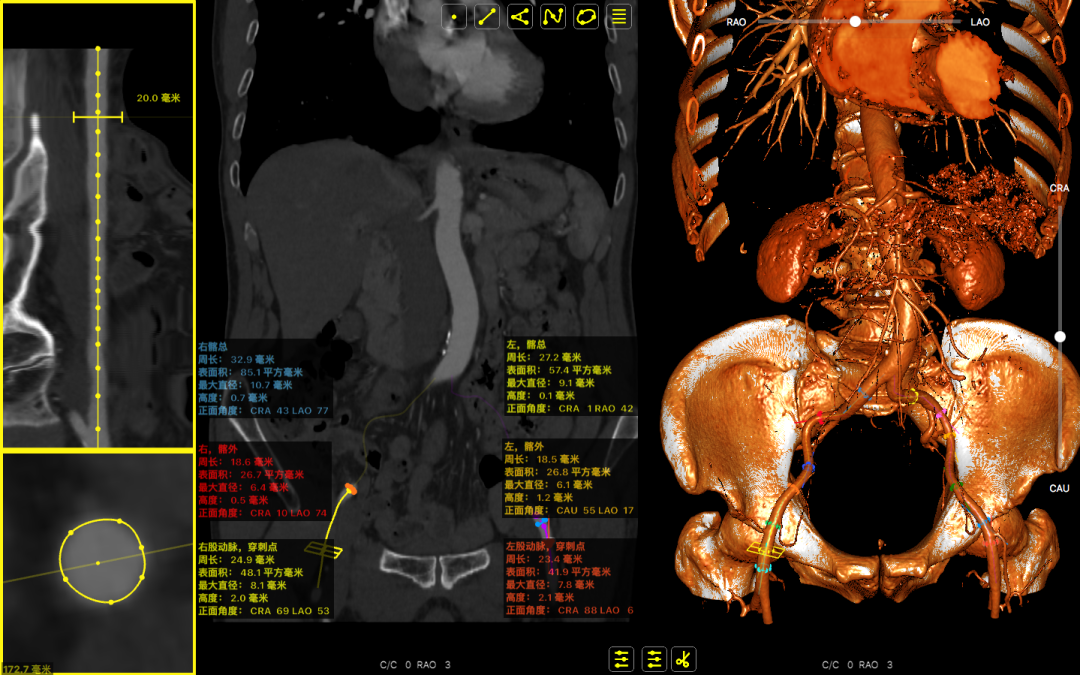

主动脉根部数据:

主动脉瓣环周长82.2mm(平均直径26.1mm),流出道周长89.6mm(平均直径28.5mm),左冠高度:15.4mm,右边冠高:14.9mm,主动脉窦宽28.7mm/33.7mm/34.9mm、STJ周长:93.5mm(平均直径29.7mm)高度22.2mm,升主动脉周长:111.7mm(平均直径35.5mm)。

术前心胸外科、心血管内科、超声科、麻醉科、体外循环、介入室等科室进行了术前讨论和术前策略分析:该患者主动脉瓣属于钙化狭窄的Type0型二叶瓣,左右冠脉同窦,无冠窦可见团状钙化,左右同窦钙化相对较少,主动脉瓣环周长82.2mm、呈现椭圆形,左室流出道周长89.6mm,主动脉窦宽28.7mm/33.7mm/34.9mm、窦宽可,STJ周长93.5mm、高度22.2mm,升主动脉周长111.7mm。患者心室壁明显增厚心尖较薄。左冠高度15.4mm右冠高度14.9mm,双冠高度可。患者右股动脉分叉点位于股骨头下缘,穿刺点内径为8.1mm,血管无明显钙化轻度迂曲。左股动脉分叉点位于股骨头下缘,穿刺点内径为7.8mm,血管无明显钙化轻度迂曲。选择右侧股动脉为主入路,左侧股动脉可作为辅入路;考虑患者主动脉瓣二叶式畸形,钙化严重,采用DOWNSIZE策略,综合评估选择20mm/22mm球囊预扩;患者瓣环周长82.2mm,考虑TAV27型号瓣膜。